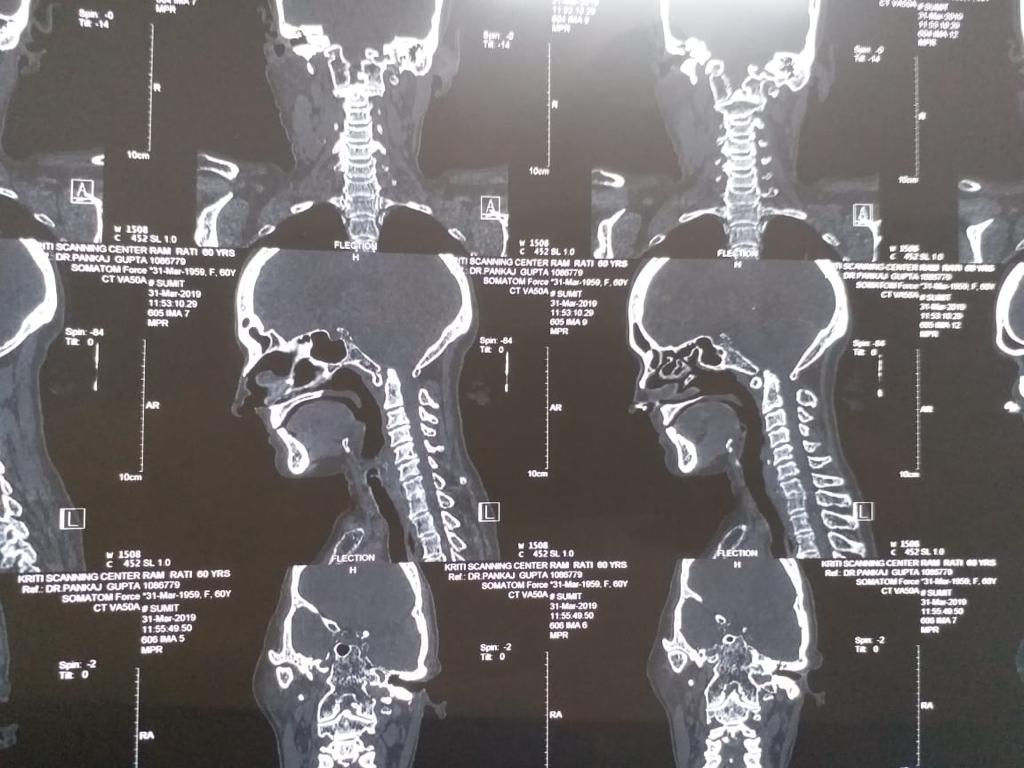

Cases